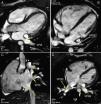

Cardiac MRI (Philips Achieva® 1.5 T system) was performed for diagnostic clarification, using balanced steady-state free precession cine sequences and phase contrast to assess valve function. Since at the time of the exam the patient was in the third month of pregnancy, it was decided not to use a contrast agent and so magnetic resonance angiography of the pulmonary veins was not possible. Cine MRI showed the right pulmonary veins, with adjacent ostia, apparently draining into the RA, while the left pulmonary veins drained normally into the LA. No atrial or ventricular septal defects were observed, but there was right chamber and venous coronary sinus dilatation and RV hypertrophy. Partial APVR was suggested as a possible explanation for the MRI findings; the echocardiographer's suspicion of persistent left superior vena cava was confirmed. Medical treatment was begun with diuretics and it was decided to continue with the pregnancy. Eight months after childbirth, cardiac MRI was repeated, this time with angiography of the pulmonary veins (Figure 1), which confirmed the diagnosis of partial APVR. The exam also showed a reduction in right chamber diameters and volumes compared to the previous MRI exam, which may be explained by the patient's pregnancy-induced hypervolemic state.

Magnetic resonance angiography of the pulmonary veins: three-dimensional images in superior (A) and posterior (B) views, confirming partial anomalous pulmonary venous return, with two pulmonary veins draining into each atrium. VPID: right inferior pulmonary vein; VPIE: left inferior pulmonary vein; VPSD: right superior pulmonary vein; VPSE: left superior pulmonary vein.

Noninvasive imaging methods are thus useful to confirm or exclude a diagnosis of partial APVR. Cardiac MRI, by combining high spatial resolution angiography and tissue characterization, is of recognized value,6–8 since, without ionizing radiation, it can delineate the anatomy of the great vessels, accurately assess pulmonary venous return and quantify the extent of left-to-right shunting. Furthermore, through analysis of the anatomy and morphology of the right chambers and of ventricular function, cardiac MRI is excellent at measuring RV volume and flow, as well as ventricular mass, thickness and contractility. Thus, MRI affords comprehensive assessment of patients with suspected partial APVR, overcoming most of the limitations of echocardiography, and can be considered a viable noninvasive alternative to cardiac catheterization to guide treatment, which can include different surgical approaches.6–9 Since the patient in the case presented was pregnant, partial APVR could only be assumed on cine MRI (Figure 3); gadolinium contrast angiography was later performed for three-dimensional assessment of the anomalous vasculature (Figure 1).

Cardiac magnetic resonance cine sequences, showing both left pulmonary veins draining into the left atrium (A and B) and both right pulmonary veins draining into the right atrium (C and D). VCI: inferior vena cava; VPID: right inferior pulmonary vein; VPIE: left inferior pulmonary vein; VPSD: right superior pulmonary vein; VPSE: left superior pulmonary vein.